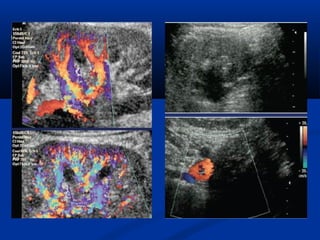

Sieâu aâmSieâu aâm

Sieâu aâm : Khoang SPMSieâu aâm : Khoang SPM